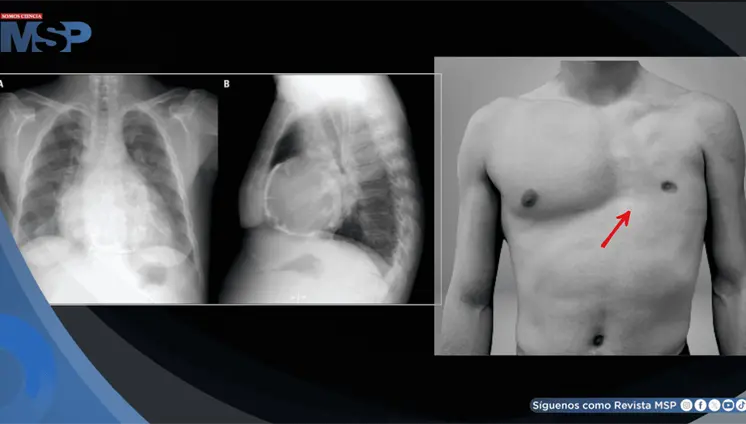

El cuadro se caracterizó por neumonía necrotizante, aleteo auricular con respuesta ventricular rápida, insuficiencia cardíaca biventricular y formación de trombos intracardíacos bilaterales.

El paciente fue dado de alta tras un accidente de tráfico sin que se sospechara daño interno, ya que solo presentaba heridas superficiales y dolor leve.

La clave estaba en entender que la tos violenta había generado una presión súbita en las arterias del cuello, causando un desgarro en la pared interna de la arteria carótida derecha.